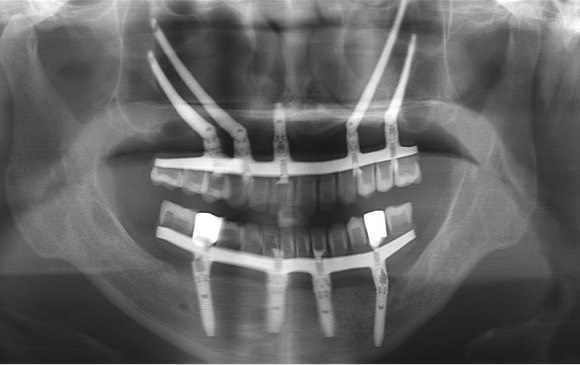

Zygoma 顴骨植體介紹

上顎骨萎縮(Maxillary atrophy)指的是骨頭消失,鼻竇氣室過大,齒槽骨嚴重萎縮甚至跟蛋殼一樣薄。有些人牙齒拔除前已經有發炎感染,拔完後甚至連骨頭都不存在。

顴骨植體手術技術是口腔重建最困難的手術之一,可以處理許多鼻竇補骨感染,植牙失敗造成齒槽骨流失的問題,建議由有經驗受過訓練的專業醫師執行。

品味牙醫使用 All-on-4 搭配顴骨植體全口重建作法,將顴骨植體卡在顴骨(Zygoma bone)最堅硬地方,當天可以裝上牙齒,平均分散咬合受力。